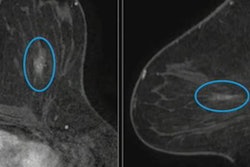

(A, B) Examples of DBT volumes containing annotated lesions that were the easiest to detect. On average, all 10 algorithms detected lesions in A and with 0.13 and 0.16 false positives, respectively. Detection bounding boxes indicate submitted algorithm predictions. The number in the upper-left corner of each box indicates the percentile of the corresponding algorithm's score with respect to the distribution of all algorithm scores for the volume. At most, two boxes per algorithm are shown, and the colors of each algorithm's boxes correspond to the free-response receiver operating characteristic curves. Images courtesy of Nicholas Konz.In the first phase of the study, teams were given 700 scans from the training set, 120 from the validation set, and 180 from the test set. The groups received the full data set in the second phase.